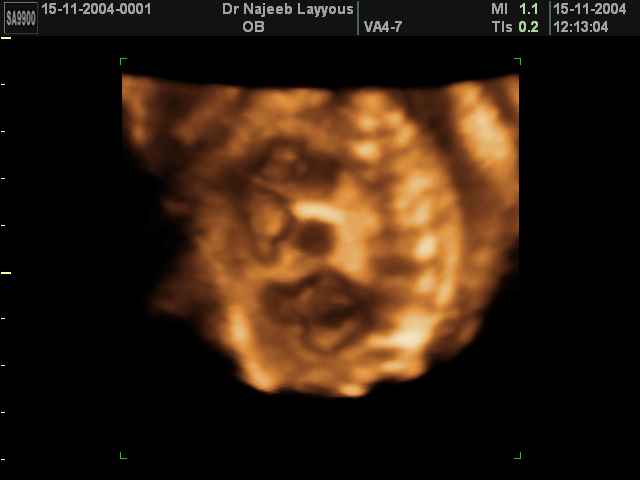

صور طبية للحمل بجهاز الالتراساوند | الدكتور نجيب ليوس